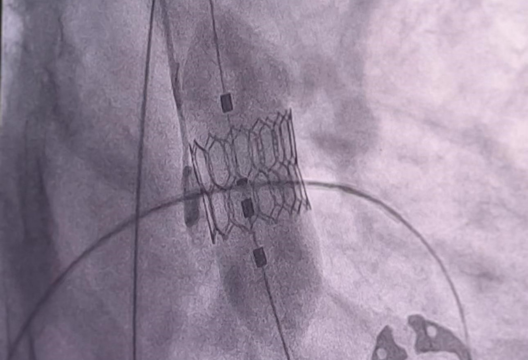

The UMC Heart Center hosted a master class on the installation of a new Octacor heart valve, which is implanted in aortic stenosis. The foreign developed device features an advanced design and is used during TAVI – transcatheter aortic valve implantation. This is a minimally invasive procedure to replace the aortic valve located between the left ventricle of the heart and the aorta. The procedure is performed by inserting a catheter through the femoral artery and is optimal for elderly patients who are contraindicated for open surgery.

“The opening of the training center will provide new opportunities for implementing advanced treatment methods for patients with structural heart diseases and for training colleagues and young specialists from other regions and countries. During the master class, we successfully performed 6 procedures for implanting a new valve and invited 15 doctors from different cities of Kazakhstan for training,” said Abdurashid Mussayev, head of the catheterization laboratory at the UMC Heart Center.